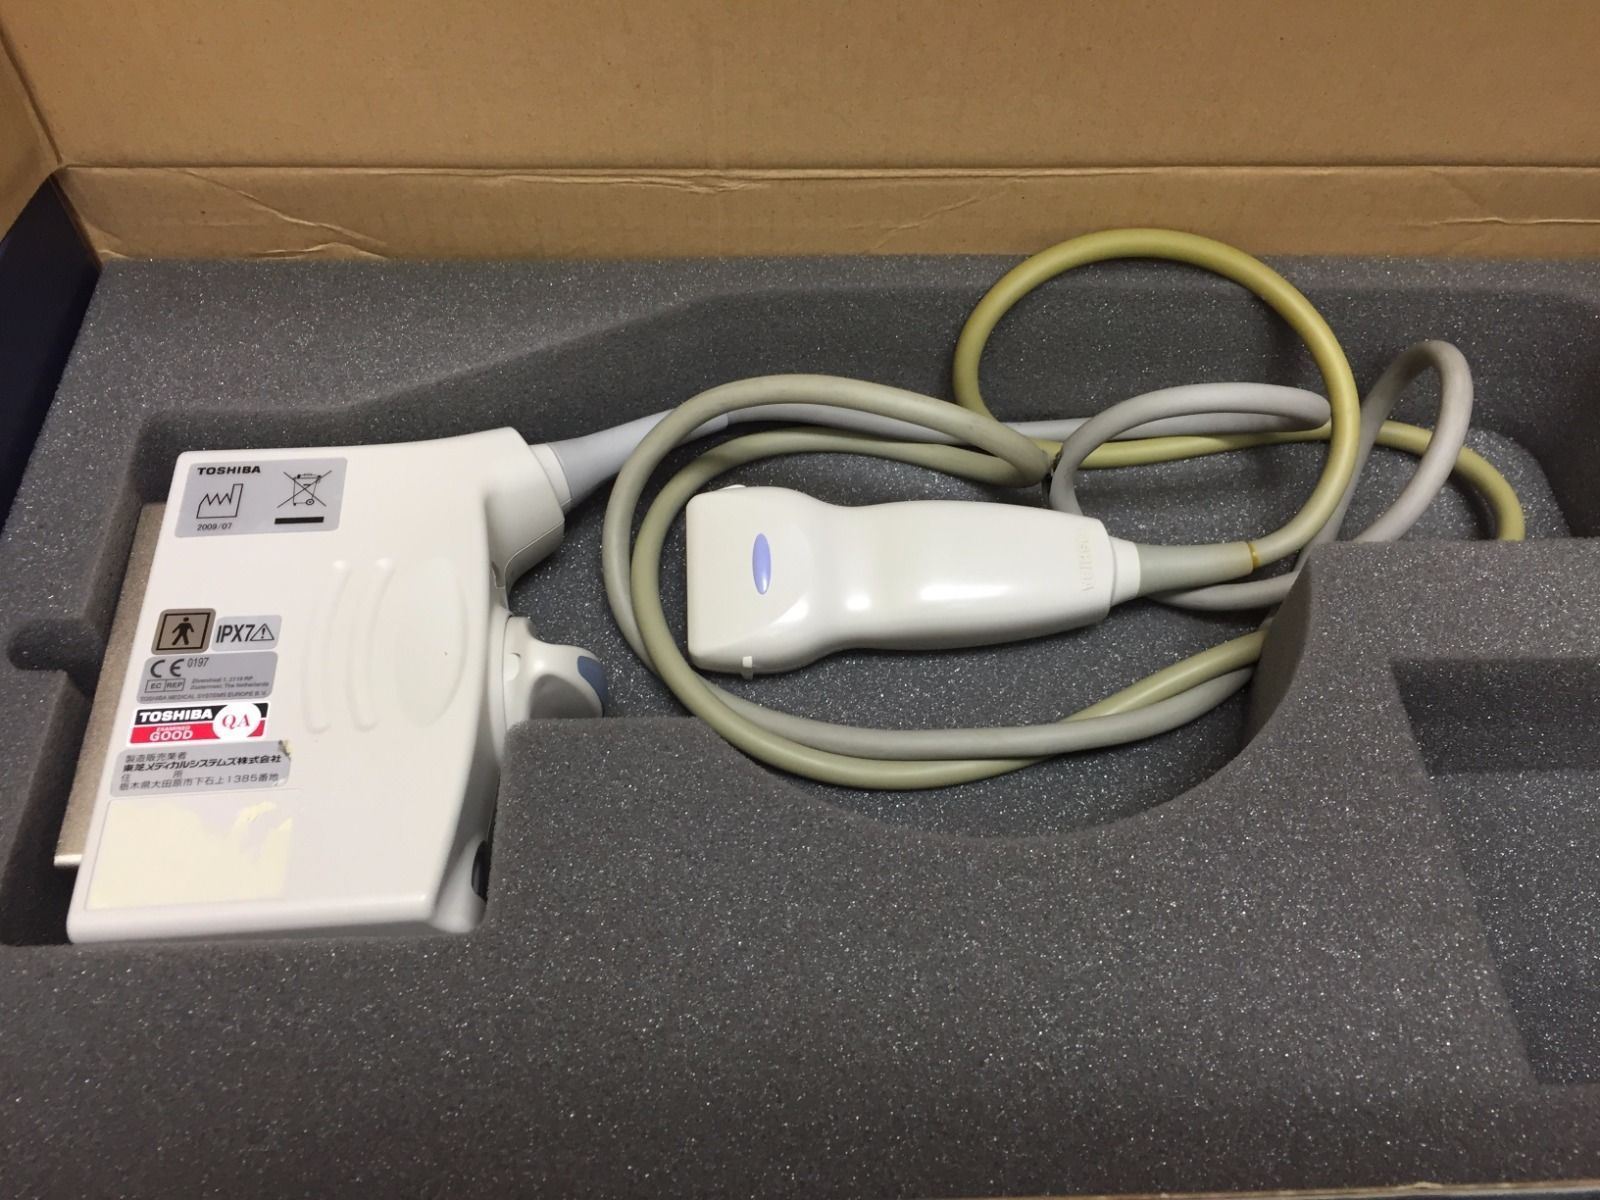

Toshiba Probes

DIAGNOSTIC ULTRASOUND MACHINES FOR SALE

Toshiba PVF-381MT 3.75 MHz Ultrasound Probe

Sale price$ 1,799.06